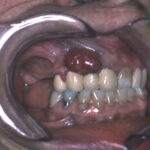

Oral mucosal melanoma= ميلانوم الاغشية المخاطية في الفم